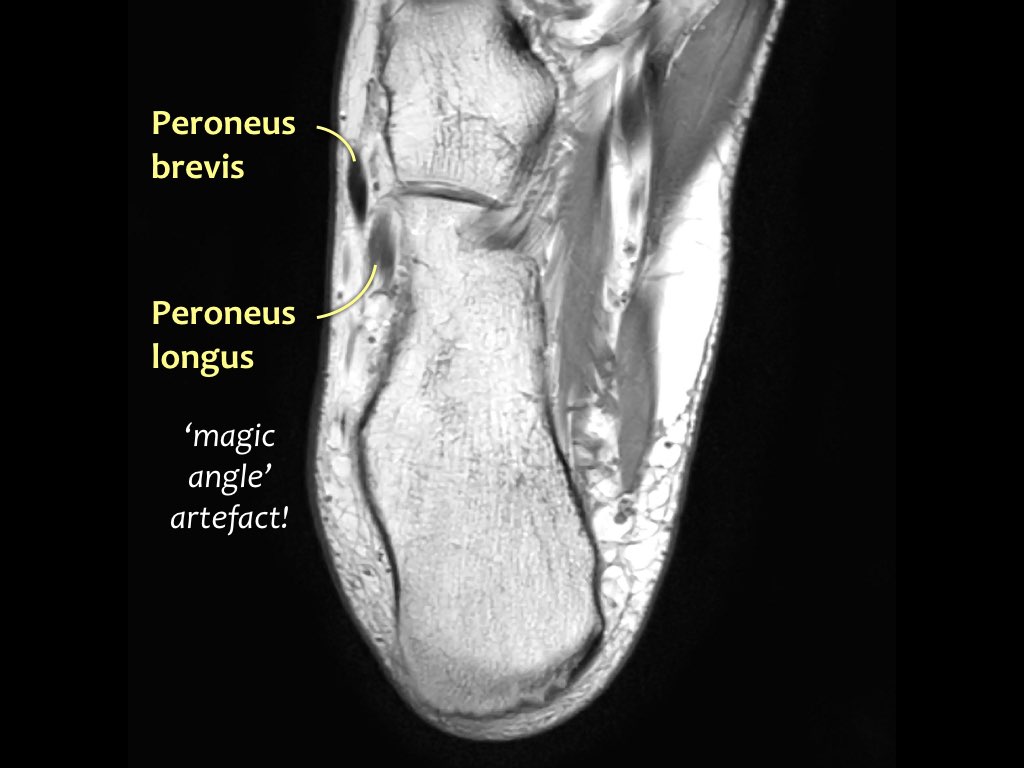

- Khoang ngoài

- Gân cơ mác dài (Peroneus Longus)

- Gân cơ mác ngắn (Peroneus Brevis)

Hướng đi của các gân dọc theo mắt cá trong và mắt cá ngoài có thể gây ra hiện tượng ‘xảo ảnh góc ma thuật’.

Các gân sẽ biểu hiện tín hiệu tăng tương đối khi tạo góc 55° so với B0, dễ nhầm lẫn với bệnh lý như viêm gân hoặc rách gân một phần.

Xảo ảnh này xuất hiện trên các chuỗi xung có thời gian TE ngắn (ví dụ: PD).

Trên các chuỗi xung có TE dài (như T2), xảo ảnh này cũng xuất hiện nhưng ít rõ rệt hơn.